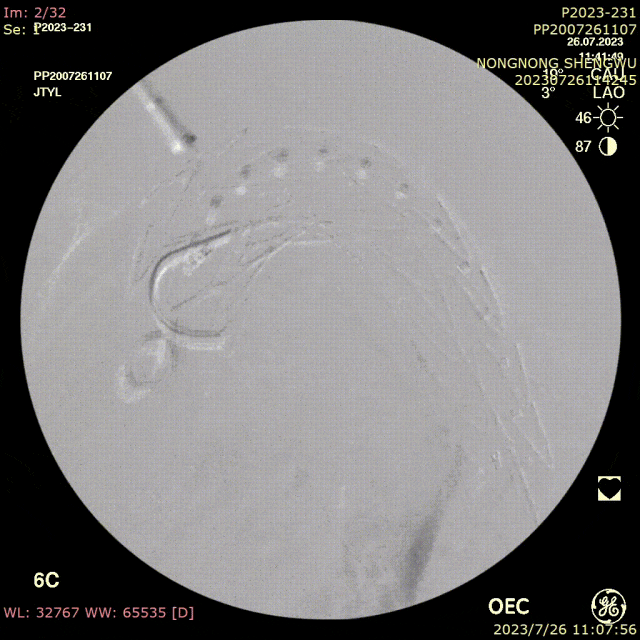

导丝破膜,各角度反复确认

破膜装置开窗

转播手术过程中即便熟练团队开窗,时间不可控,导丝穿破FUSTAR